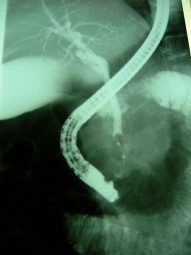

Coledocolitiasis pancreatitis biliar

Envíado por Dr. Carlos Miguel Zavaleta Consuegra